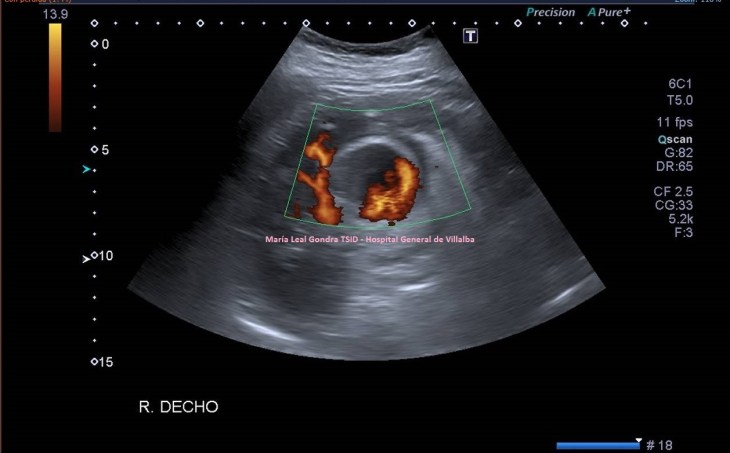

En la imagen 3,4 y 5 ves una lesión en la misma localización, ecogénica, sólida, heterogénea, redonda y de gran tamaño, lobulada. Tiene vascularización y es heterogénea. Flecha amarilla.

Ambas lesiones ubicadas en el polo superior del riñón derecho. más profundo que el polo inferior, normal, desde el punto de vista ecográfico, según la disposición de la sonda y la situación espacial del riñón en la anatomía humana de modo general, siempre a expensas de rotaciones y variantes de la normalidad.

3

4

5

La semiología nos sirve para identificar lesiones, que la radióloga pueda discernir si éstas, por su aspecto ecográfico, son o no son compatibles con malignidad y en este caso ampliar el estudio si lo considerase oportuno con CT o RMN.

Nos quedamos con la imagen 3 y 4, y en este caso observamos que es una lesión que la paciente ya tenía años atrás y que fue objetivada ecográficamente, de menor tamaño y que en tres años ha crecido considerablemente y que no ha sido tratada durante este tiempo por motivos que desconozco.